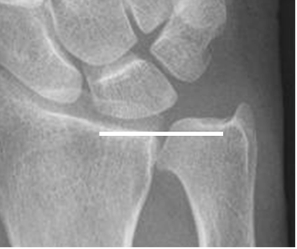

En la varianza ulnar positiva, la ulna es mas larga y se asocia con síndrome de impactación (Fig 13)y en la negativa, la ulna es mas corta, asociándose a enfermedad de Kienböck.(Osteonecrosis del semilunar). (6). (Fig 14).

Fig 13. Varianza ulnar positiva.

Rx AP. Varianza ulnar positiva, con extremo de la ulna mas largo que el radio.